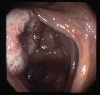

Campylobacter colitis of the ileo-cecal valve.

Tokyo Pref., Cooperative study between National Cancer Center and Kyushu Cancer Center